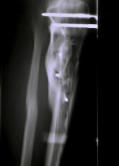

(1998) Bild 1 Komplizierter Splitterbruch vor klinischer Versorgung, Bild 2 vor Therapiebeginn. Bild 3 - 8 Heilungsverlauf.

Bild 1 Komplizierter Splitterbruch vor klinischer Versorgung,

Bild 2 vor Therapiebeginn. Bild 3 - 8 Heilungsverlauf.

(1998) Bild 1 Komplizierter Splitterbruch vor klinischer Versorgung,

Bild 2 vor Therapiebeginn. Bild 3 - 8 Heilungsverlauf.